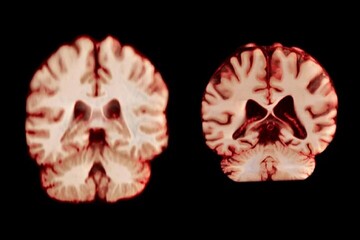

مغز مردان سریعتر از زنان کوچک میشود

مغز زنان کُندتر پیر میشود، اما به نظر نمیرسد که این موضوع آنها را از ابتلا به نوع شایع زوال عقل محافظت کند.